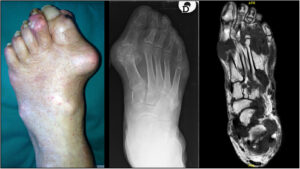

6. Gout in the Ankle

Gout in the ankle causes sudden, intense pain and inflammation due to uric acid crystal buildup. Attacks often occur at night and may be mistaken for sprains or infections.

Symptoms include:

• Severe pain and redness

• Swelling and warmth

• What does gout feel like in the ankle—often described as stabbing or crushing pain

Common searches include:

• What causes gout in the ankle

• Can you get gout in your ankle

• Home remedies for gout in the foot and ankle

• Gout in the ankle treatment

Prompt treatment is essential to prevent joint damage and recurring attacks.